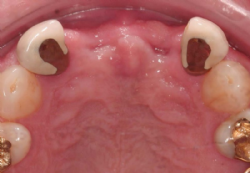

Abbildung 2: Situation von okklusal vor und nach der Augmentation